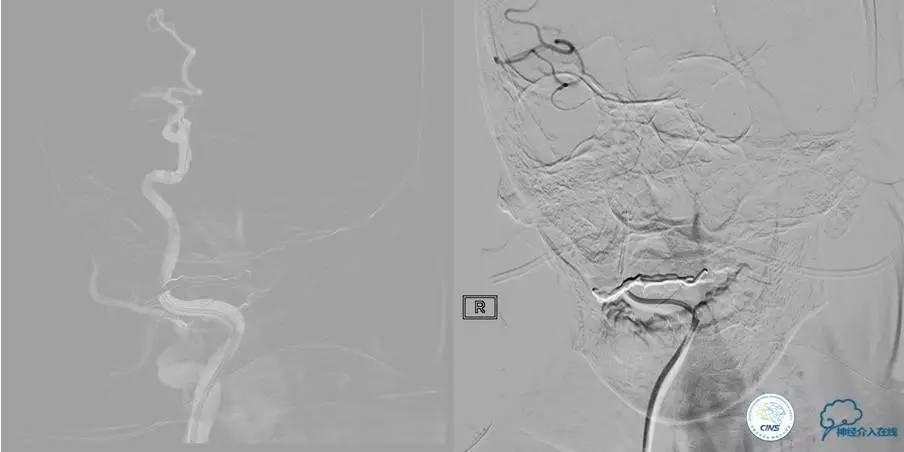

尿激酶20万单位,动脉导管内推注。

口服拜阿司匹林300mg,再次取栓。

2.0×15mm球囊扩张V4段狭窄。

Penumbra 导管再次取栓。

▼R-VA